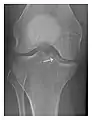

Figure 9: Proximal metaphyseal fatigue fracture of the tibia in a 27-year-old recent male military recruit. (a) Anteroposterior radiograph is within normal limits. (b) Coronal T1-weighted MR image shows a marked linear hypoattenuation along the medial tibial metaphysis (arrow) surrounded by diffuse hypointensity in keeping with posttraumatic edema.[1]

a

b